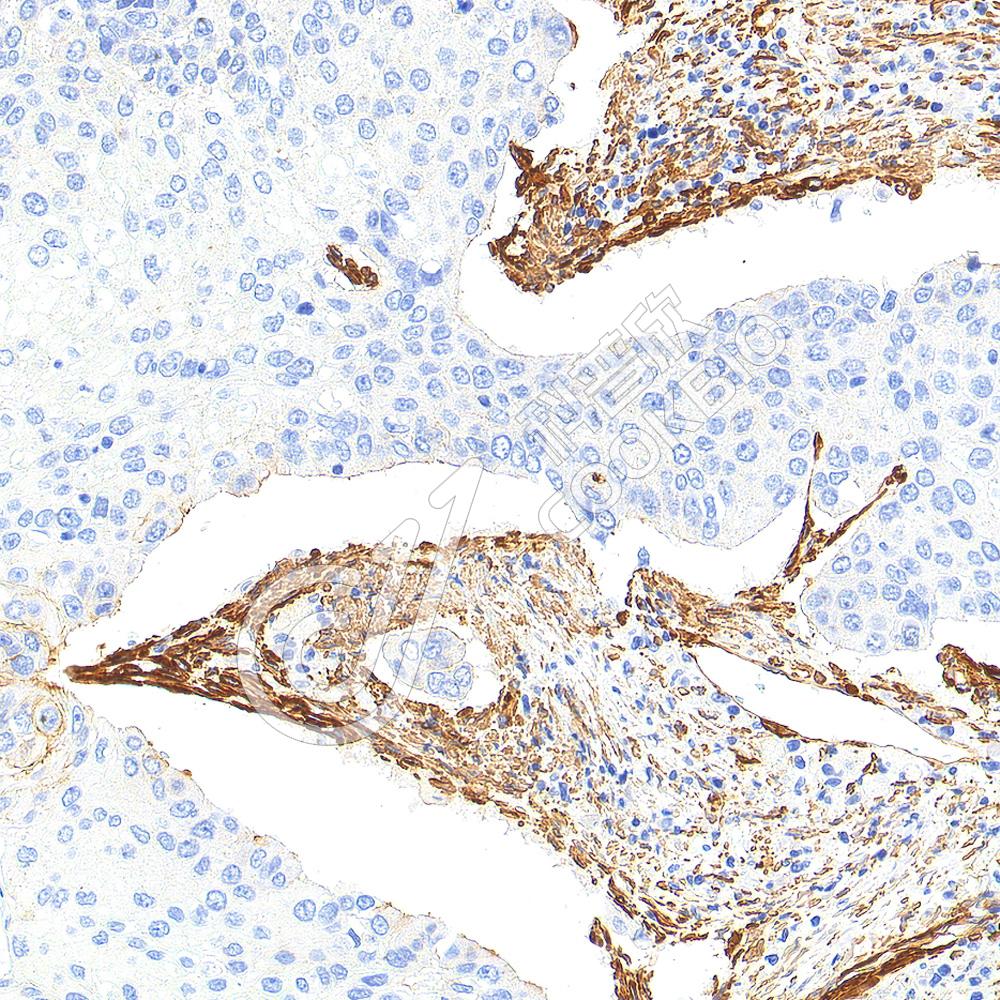

IHC检测ATP5A蛋白(货号 K5460365).

样品: 大鼠肾, 4%多聚甲醛 (货号KSG1101) 固定12-24小时.

抗原修复: Tris-EDTA抗原修复液(pH 9.0) (KSG1203), 100℃, 25分钟.

—抗: 1: 2000稀释, 4℃ 孵育过夜.

二抗: S-vision免疫组化多聚二抗(山羊抗小鼠), 即用型(货号KB3903), 室温孵育20分钟.